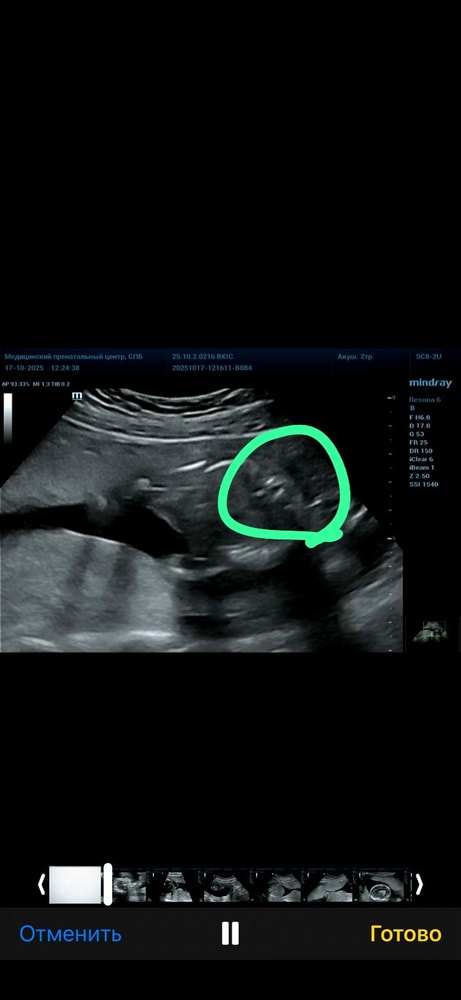

хочу выслать фото с узи, конечно понимаю что не все поймут узи, но вдруг у кого-то было похожее.